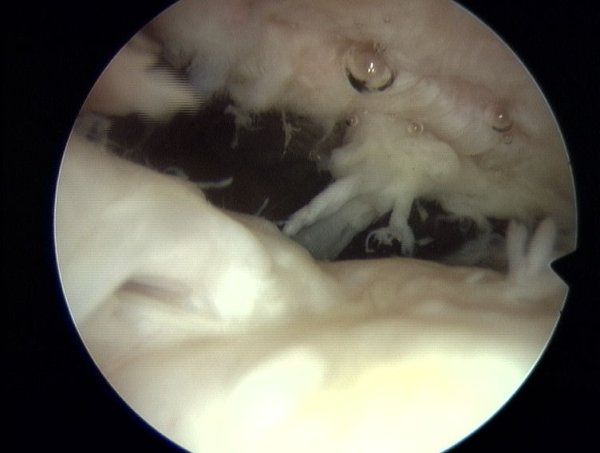

Tu zerwanie widoczne z regionu podbarkowego ze sciegnem miesnia dwuglowego ( po prawej stronie)

Normalny wygląd przyczepu mięśnia nadgrzebieniowego (m.supraspinatus), z lewej strony ścięgno mieśnia dwugłowego (m.biceps brachii), na dole głowa kości ramiennej. Na zdjeciu rentgenowskim na niebiesko.

Zerwanie widziane podczas artroskopii ( małe i duże).